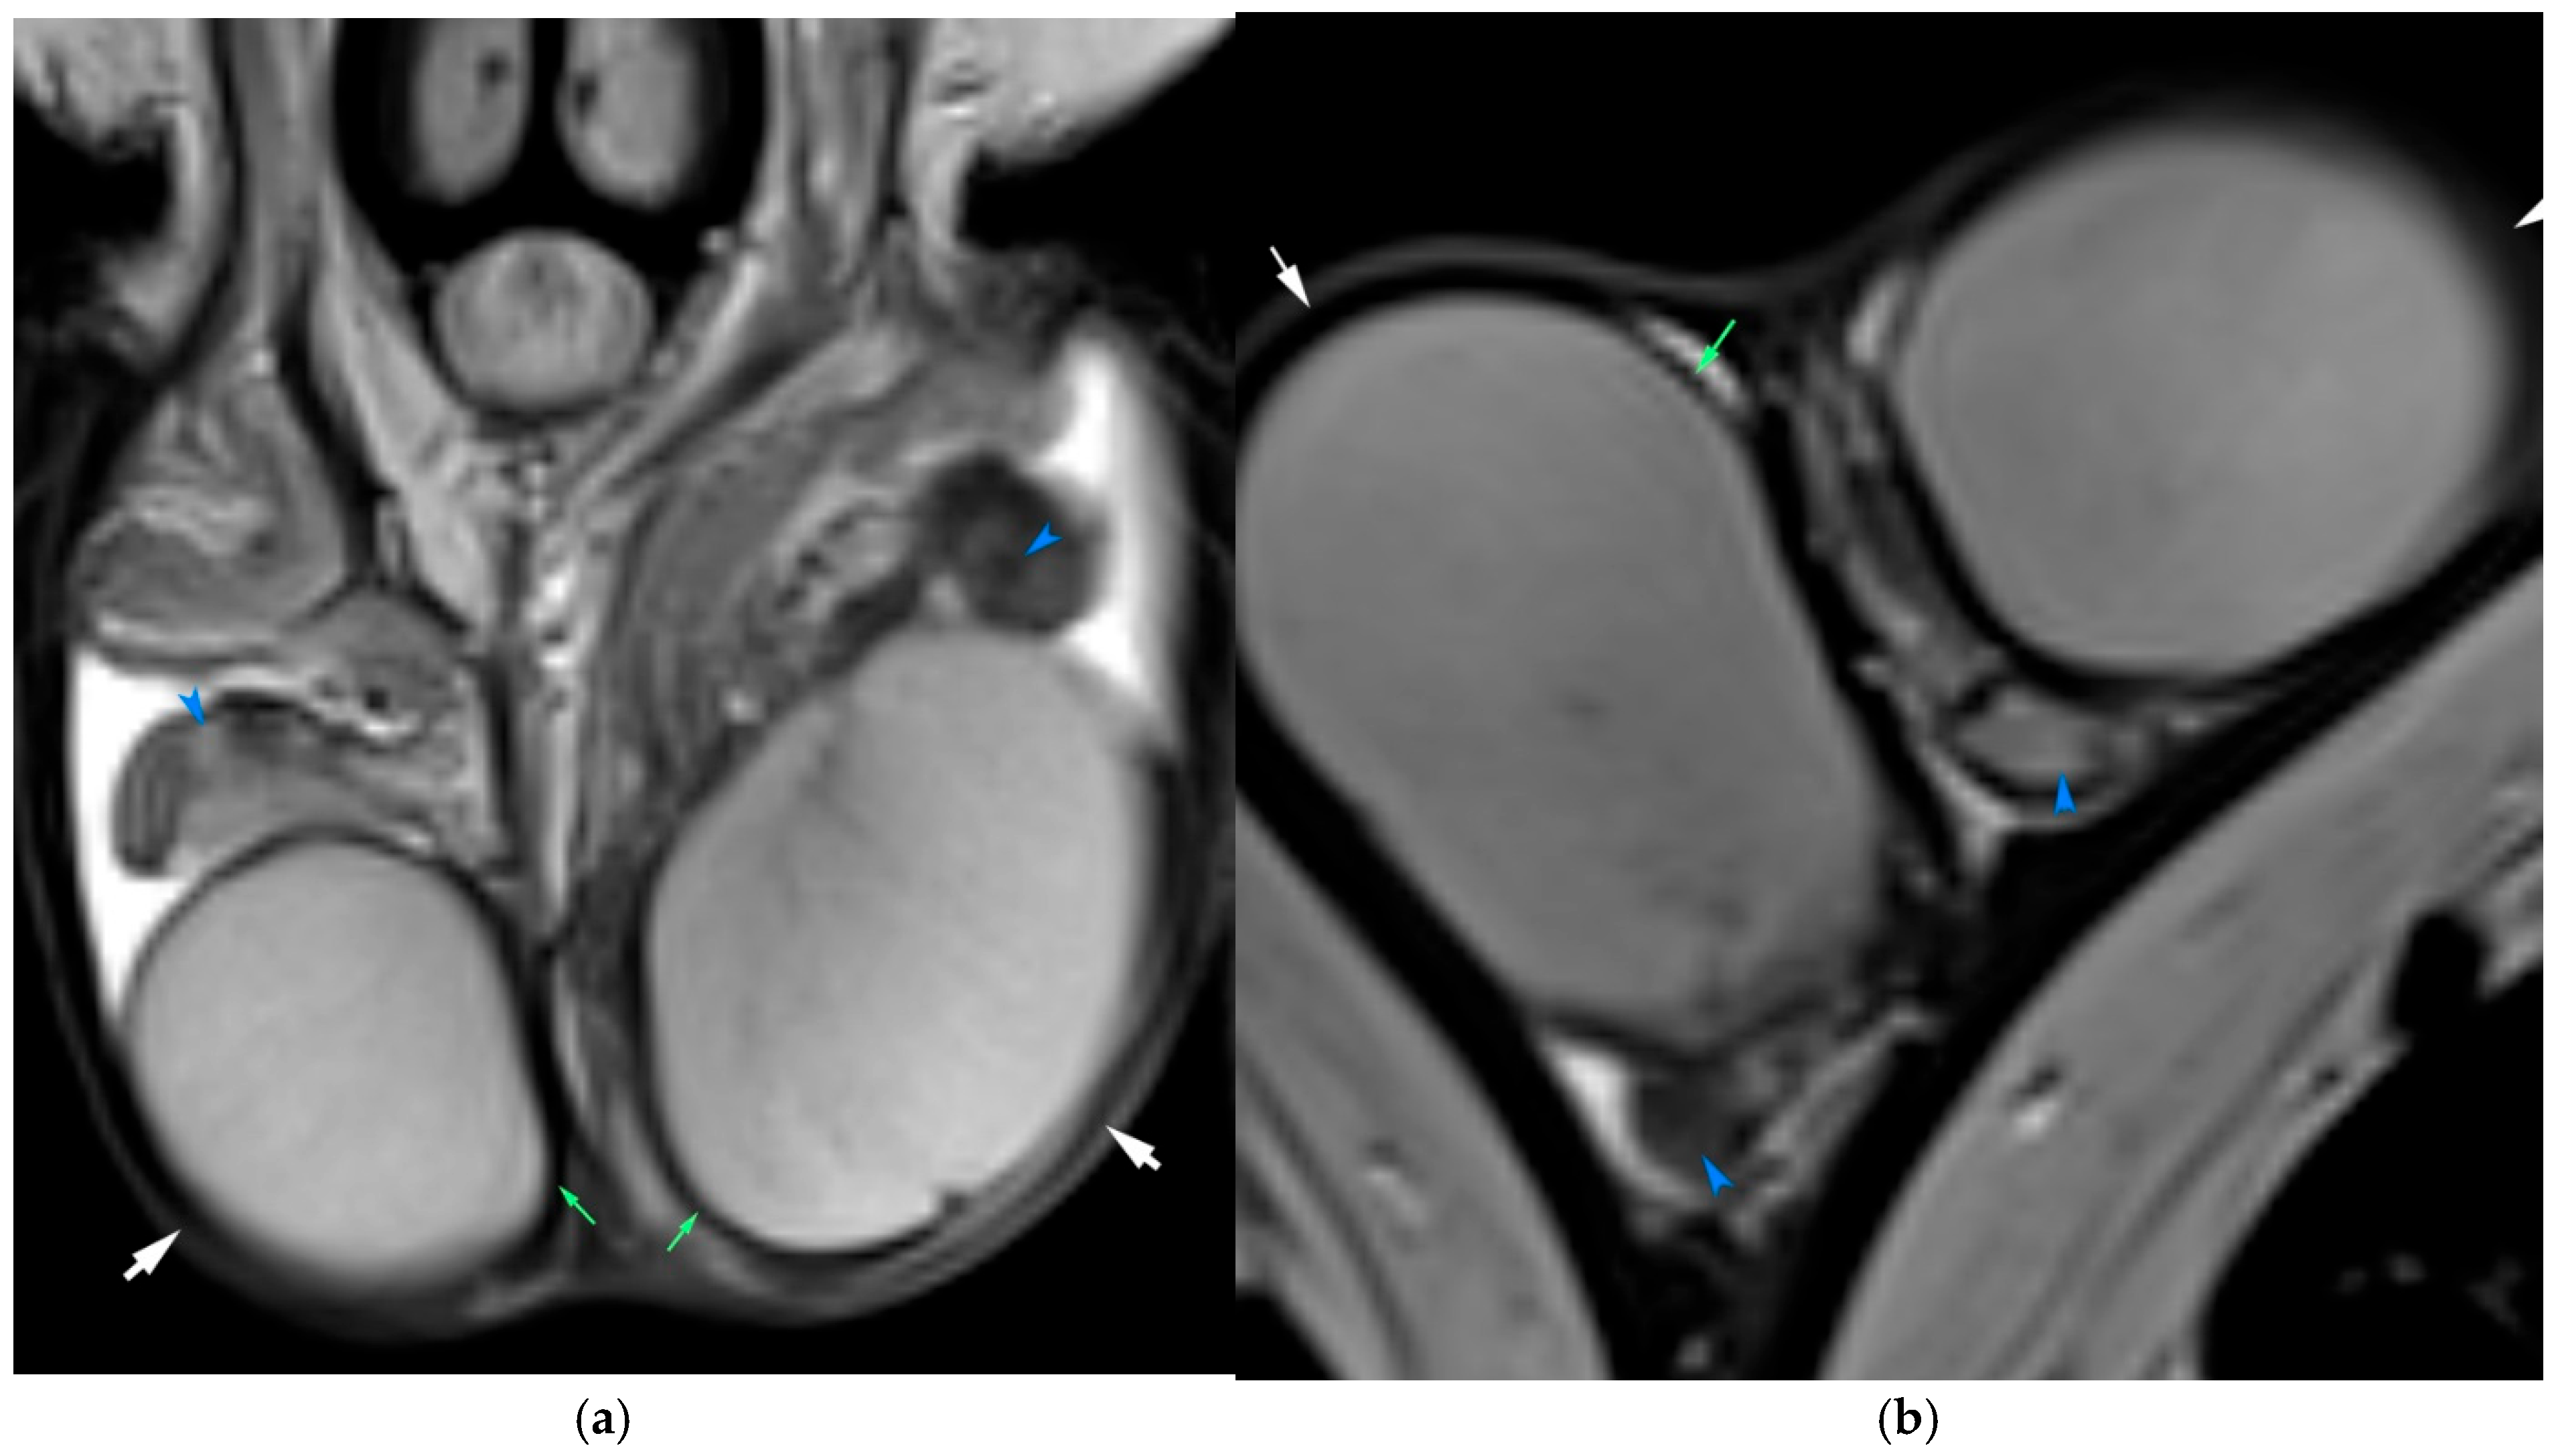

3.1. Torsion and Trauma

3.2. Inflammation and Infection